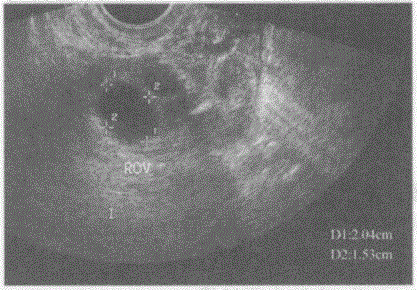

临床资料:女,27岁,自述月经周期第12天,行卵泡监测。超声综合描述:经阴道扫查右卵巢内可见2.0cm×1.5cm无回声区,边界清晰,形态规则。 ...

问题 临床资料:女,27岁,自述月经周期第12天,行卵泡监测。 超声综合描述:经阴道扫查右卵巢内可见2.0cm×1.5cm无回声区,边界清晰,形态规则。 超声提示:

选项 A.右卵巢囊肿 B.右卵巢优势卵泡 C.盆腔包裹性积液 D.右输卵管积液

答案 B